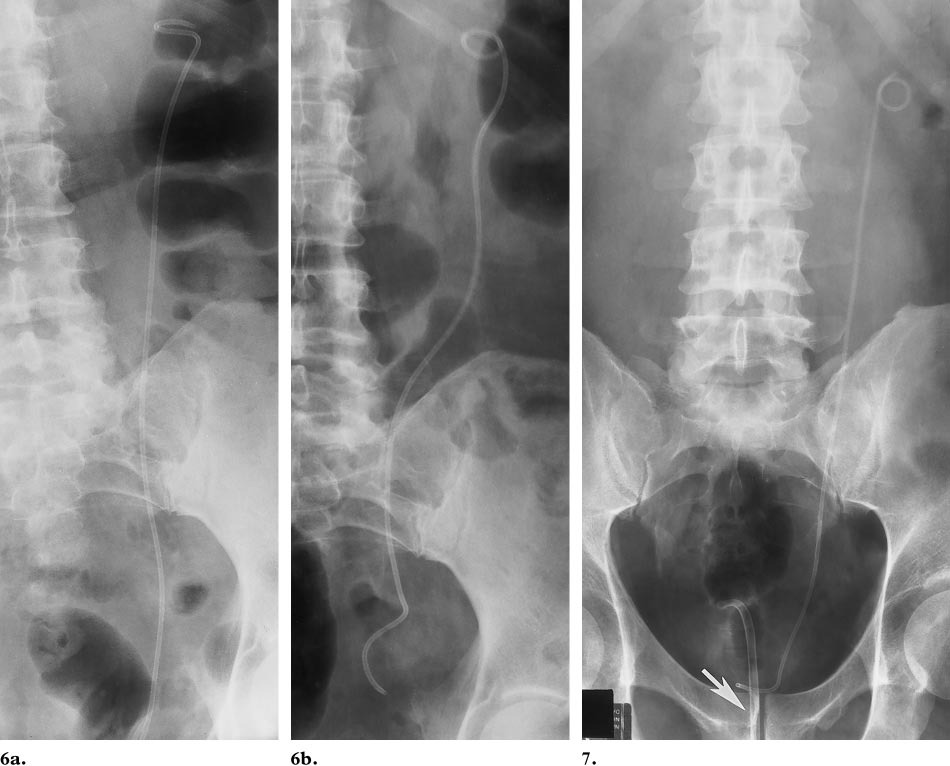

2. 双“J”管放在哪里?

双“J”管有两端,头端位于肾脏(多位于肾盂),尾端位于膀胱,中间的管体位于整个输尿管管腔内。

(5) 移位、脱位:置管不到位,患者的剧烈活动,输尿管蠕动收缩导致双J管上移或者下移。若发现双J管脱落,请及时带管回院就诊。